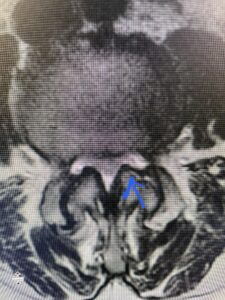

Another patient is a 62 year-old female with progressive low back pain and right leg pain and numbness that radiates to the top of her foot. She tried physical therapy and epidural injections. MRI demonstrated severe L3-4 stenosis and a grade 1 spondylolisthesis (Fig 4). There was L5-S1 and L4-5 disc collapse with modic end-plate changes. Biomechanically because of the significant degeneration of these disc spaces which stiffened the L4-S1 segment more stress was placed on the L3-4 segment, resulting in significant premature degeneration and compensatory stenosis and segmental instability. The MRI also showed pathologically, because of the slip, the L3 inferior processes were more anteriorly oriented and hence contributing to the majority of the lumbar canal compromise. Note the more sagittally-oriented facets in this case compared to the prior case (Fig 5). The patient underwent a decompressive laminectomy with attention of removing the inferior processes of L3 to fully decompress the canal. We also performed an L3-4 fusion with instrumentation (Fig 6). The patient had an uneventful postoperative course with improvement of leg pain. Of note with relief of the disabling leg pain patients are generally very happy. Patients can often manage their low back pain; it is the leg pain that they just can’t tolerate.

Fig 4: Sagittal T2-weighted lumbar MRI demonstrating L3-4 grade 1 spondylolisthesis with severe stenosis (blue arrow)